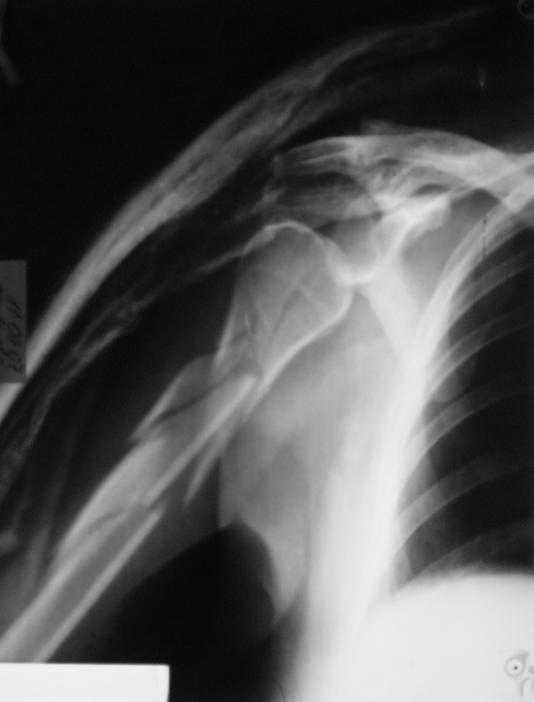

Многооскольчатый перелом плечевой кости в В/3

Ув. коллеги, со стационара в поликлинику пришла женщина, 48 лет, травма 29.08.07 лечение консервативное в гипсовой повязке.

Оперативное лечение не предлагалось. Обыективно - правая верхняя конечность в гипсовой лангете едва прикрывающей правый плечевой сустав.

Немножко переделал повязку с отведением, подправил, вот что получилось.

Перелом внутрисуставной, Вы уверены на счет Сармиенто? На первичном снимке не видно было перелома головки.